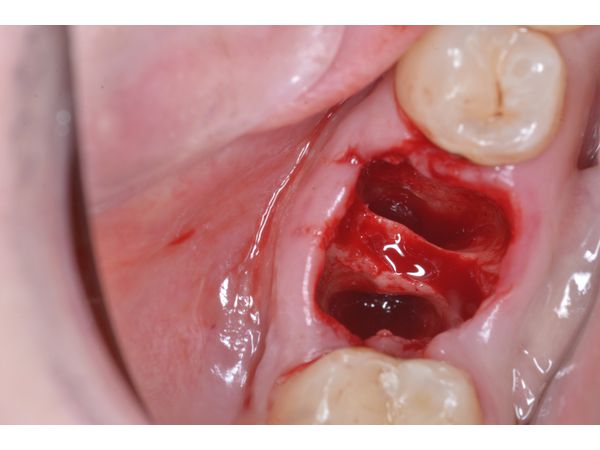

1. Произведено атравматичное удаление 4.6 зуба с разобщением корней при помощи фрезы, через лунку зуба удалены грануляции, выполнена антисептическая обработка.